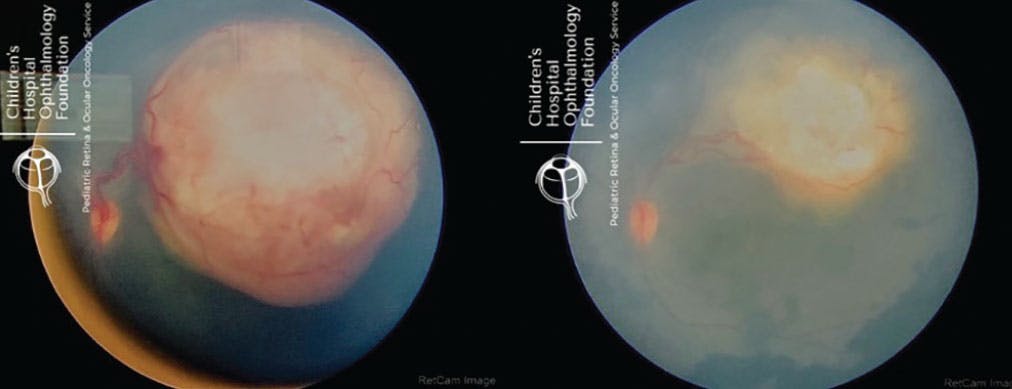

<p>Figure 1. Dyskeratosis congenita with bilateral retinal exudates and angiographic leakage.</p>

Figure 1. Dyskeratosis congenita with bilateral retinal exudates and angiographic leakage.

At Boston Children’s Hospital, we see considerable medical and surgical volume consisting of a variety of ocular conditions, including retinopathy of prematurity, familial exudative vitreoretinopathy, pediatric retinal detachment, persistent fetal vasculature, dyskeratosis congenita, incontinentia pigmenti, Coats disease, and proliferative sickle cell retinopathy (Figures 1-3).